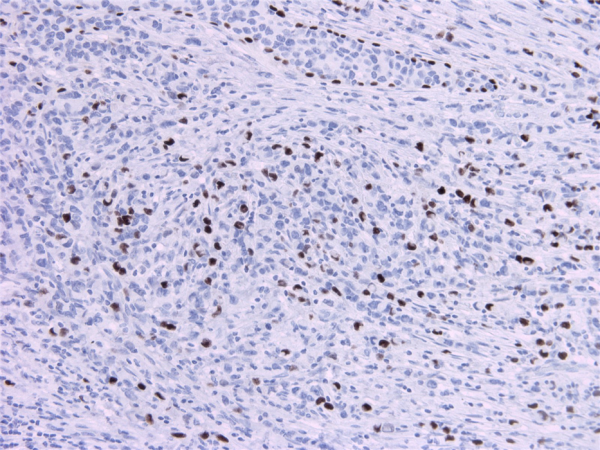

Produktinformationen "Anti-P63"

The p63 gene is a homologue of the p53 tumor suppressor gene. Like p53, p63 contains a transactivation (TA) domain induce the transcription of target genes, a DNA binding domain, and an oligomerization domain (OD), used to form tetramers. In contrast to p53, the p63 gene encodes for at least six major isotypes. Three isotypes (TAp63alpha, TAp63beta, and TAp63gamma) contain the transactivating (TA) domain and are able to transactivate p53 report genes and induce apoptosis. In contrast, the other three isotypes (deltaNp63alpha, deltaNp63beta, deltaNp63gamma) are transcribed from an internal promoter localized within intron3, lack the TA domain, and act as dominant-negatives to suppress transactivation by both p53 and TAp63 isotypes. p63 is highly expressed in the basal cells of the epithelium significant for proper limb outgrowth and morphogenesis.4 In differentiating tissues, p63 is crucial for maintaining the stem cell identity of the basal cells, and is indispensable for correct development of the skin as well as the limb. p63-deficient mice lack all squamous epithelia and their derivatives, including hair, whiskers, teeth, as well as mammary, lacrimal, and salivary glands.Tissue specificity: Widely expressed, notably in heart, kidney, placenta, prostate, skeletal muscle, testis and thymus, although the precise isoform varies according to tissue type. Progenitor cell layers of skin, breast, eye and prostate express high levels of DeltaN-type isoforms. Isoform 10 is predominantly expressed in skin squamous cell carcinomas, but not in normal skin tissues Control: Tonsil, prostate. Protein function: Acts as a sequence specific DNA binding transcriptional activator or repressor. The isoforms contain a varying set of transactivation and auto-regulating transactivation inhibiting domains thus showing an isoform specific activity. Isoform 2 activates RIPK4 transcription. May be required in conjunction with TP73/p73 for initiation of p53/TP53 dependent apoptosis in response to genotoxic insults and the presence of activated oncogenes. Involved in Notch signaling by probably inducing JAG1 and JAG2. Plays a role in the regulation of epithelial morphogenesis. The ratio of DeltaN-type and TA*-type isoforms may govern the maintenance of epithelial stem cell compartments and regulate the initiation of epithelial stratification from the undifferentiated embryonal ectoderm. Required for limb formation from the apical ectodermal ridge. Activates transcription of the p21 promoter. [The UniProt Consortium]

| Anwendung: | IHC (paraffin) |